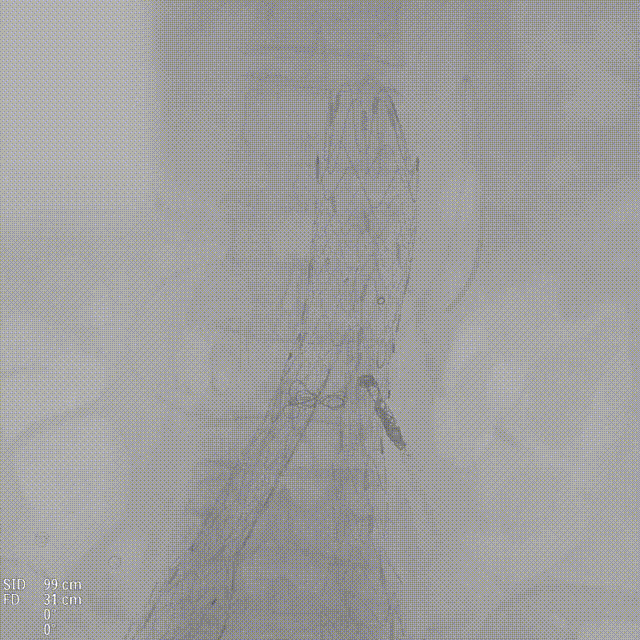

造影:支架定位准确,形态良好,未见明显受压。双侧肾动脉显影同前,原主动脉及双侧髂动脉血流通畅,至延迟相瘤腔内未见明显内漏,左侧髂内动脉显影可。

gore医疗怎么样「漫腹精论」独具匠心 推陈出新——同侧IBE支架内翻山重建髂内动脉治疗EVAR术后内漏病例报道_https://www.jmylbn.com_新闻资讯_第21张

术后造影

gore医疗怎么样「漫腹精论」独具匠心 推陈出新——同侧IBE支架内翻山重建髂内动脉治疗EVAR术后内漏病例报道_https://www.jmylbn.com_新闻资讯_第22张

术后髂动脉造影